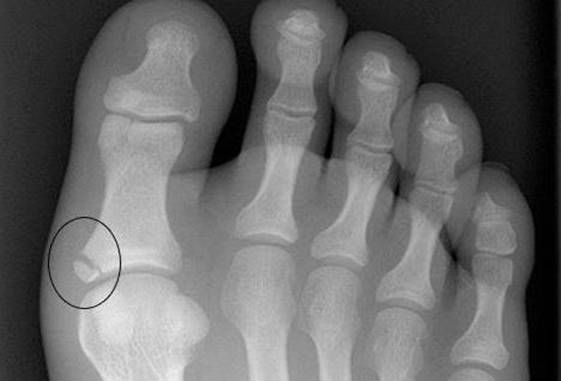

Из инструментальных методов в диагностике перелома пальцев стопы чаще всего используется рентгенографическое исследование.

Снимки делают в прямой, боковой, а также косых (в сомнительных случаях) проекциях. При этом выявляют нарушение целостности фаланги пальца, его характер, состояние краев костных отломков, которые образовались в момент травмы.

Другие методы инструментальной диагностики в массовом порядке не привлекают – рентгенографического обследования достаточно, чтобы выявить перелом, оценить его характеристики и принять решение про конкретный метод лечения. Если по техническим причинам, а также из-за анатомических особенностей пациента рентгенография неинформативна, то привлекается компьютерная томография (КТ) – компьютерные срезы позволяют рассмотреть место перелома, «разворачивая» в разные стороны изображение стопы на экране компьютера.